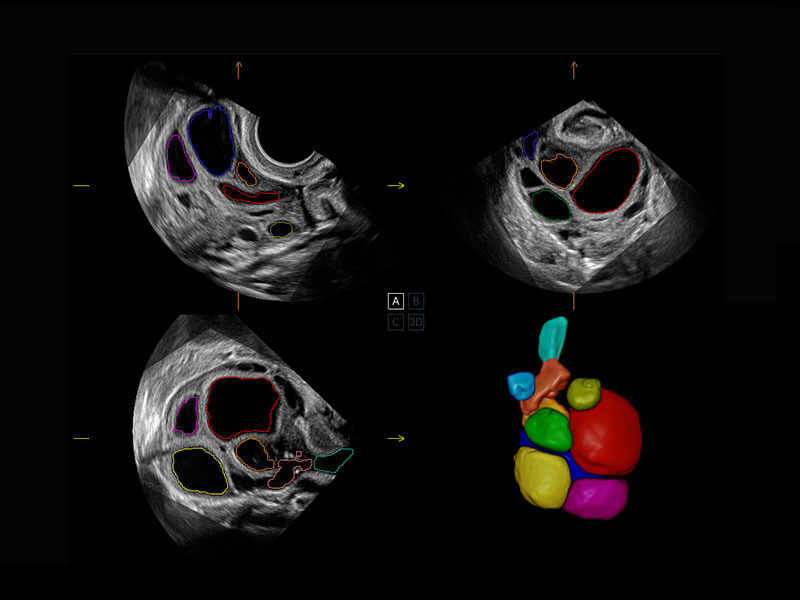

乳腺超声 / 新生儿

P60搭载宽频带线阵探头、宽景成像、弹性成像技术,为您提供乳腺全面应用方案。P60支持高频相控阵探头、线阵探头、腹部高频探头、腹部微凸探头等,丰富的探头群搭载敏感的彩色血流成像,适用于新生儿多种脏器检测要求,满足新生儿筛查需求。

• 新生儿心脏